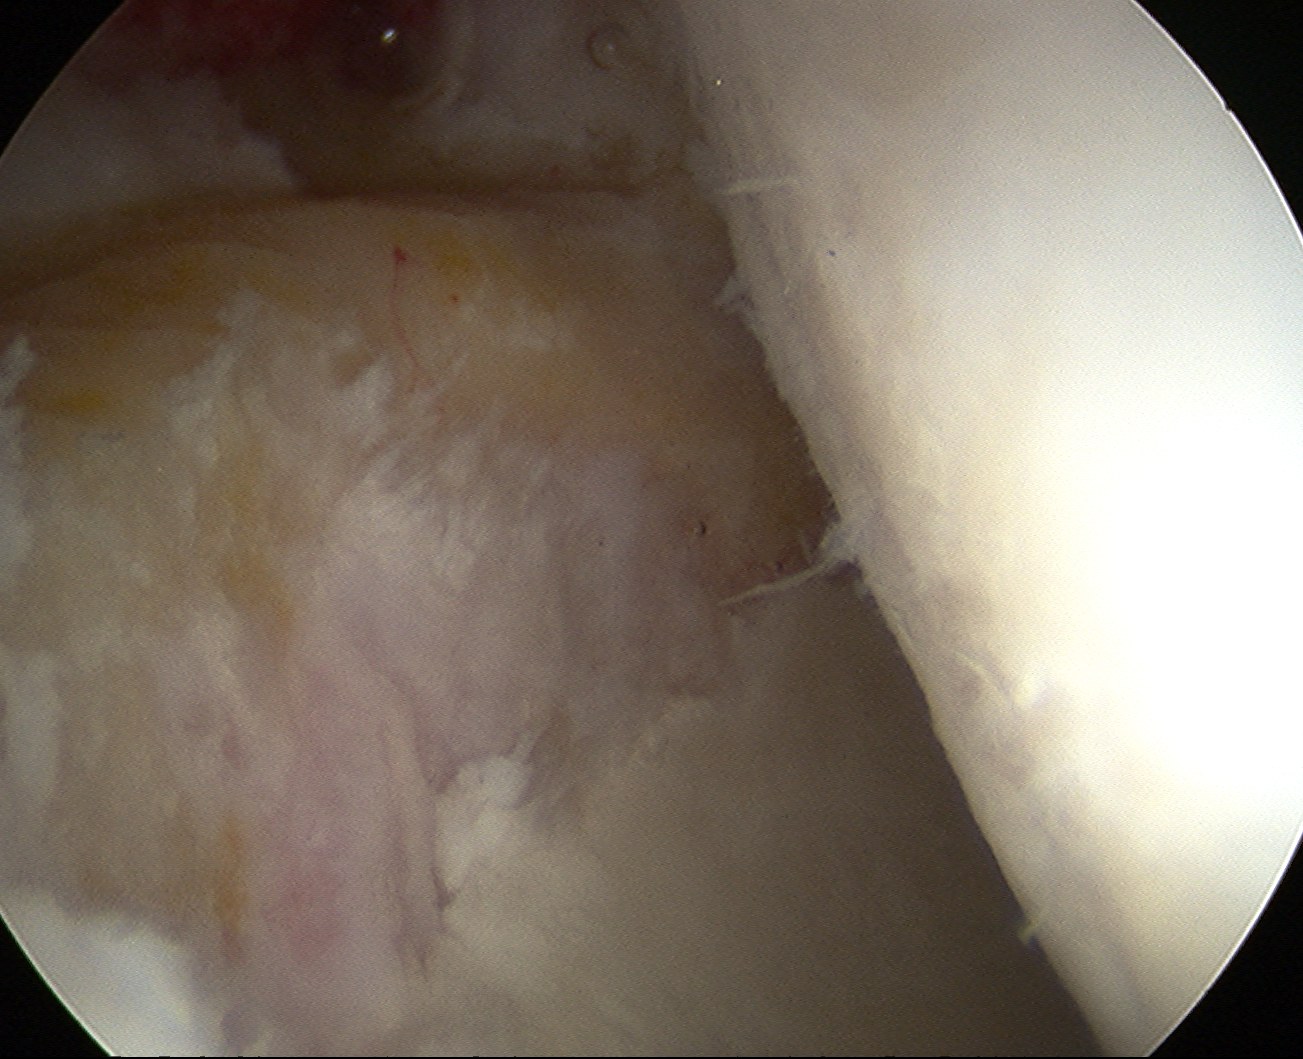

MRI

Labral tears

Best seen on coronal MRI

Saied et al BMC Musculoskeletal Disorders 2017

- systematic review

- labral tears: MRI sensitivity 86% and specificity 83%

- chondral lesions: MRI sensitivity 87% and specificity 72%

- labral tears: MRA sensitivity 91% and specificity 58%

- chondral lesions: MRA sensitivity 75% and specificity 79%